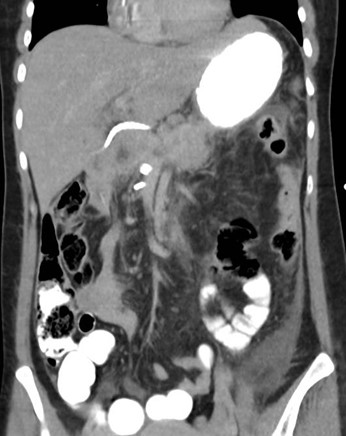

Tomografía de abdomen y pelvis con cte ev: del 13/10/2023.

Complicaciones posquirúrgicas

Tomografía de abdomen con cte ev: del 20/10/2023.

Tomografía de abdomen con cte ev: del 26/10/2023.